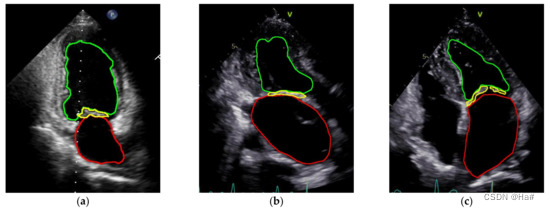

3、超声心动图分割

二尖瓣反流分类:心尖两腔,心尖三腔,心尖四腔

网络:VDS-UNET;VGG16

提取视频若干帧,图像分割

(a) 两个顶腔的标记;(b)顶点三腔标记;(c)顶端四室标记。

4、超声心动图检查风湿性心脏病的自动诊断

数据集由 11 646 个 MP4 格式(分辨率 320 × 240 像素)的超声心动图视频组成

网络:3D 卷积神经网络 (C3D) 解决了 RHD 识别

工作:将C3D性能与超声心动图文献中常用的 2D 卷积神经网络 (VGG16) 进行了比较